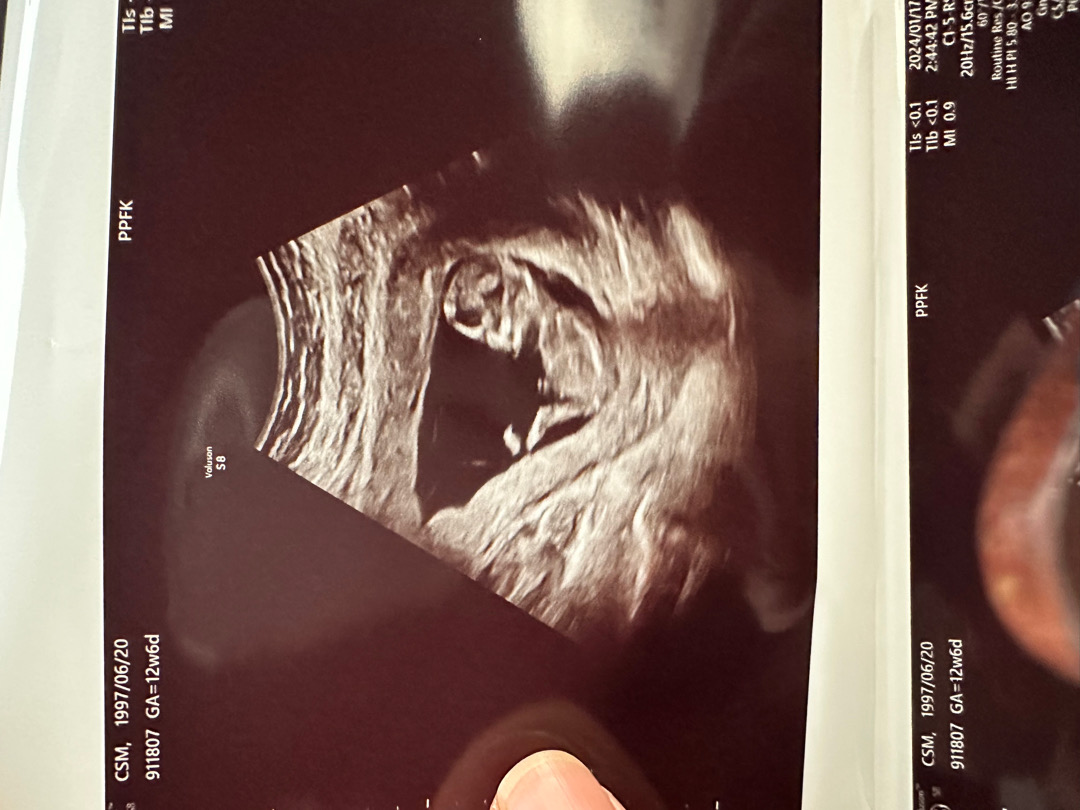

각도법 볼수있을까여~?

이사진으로 각도법 볼수있을까요??